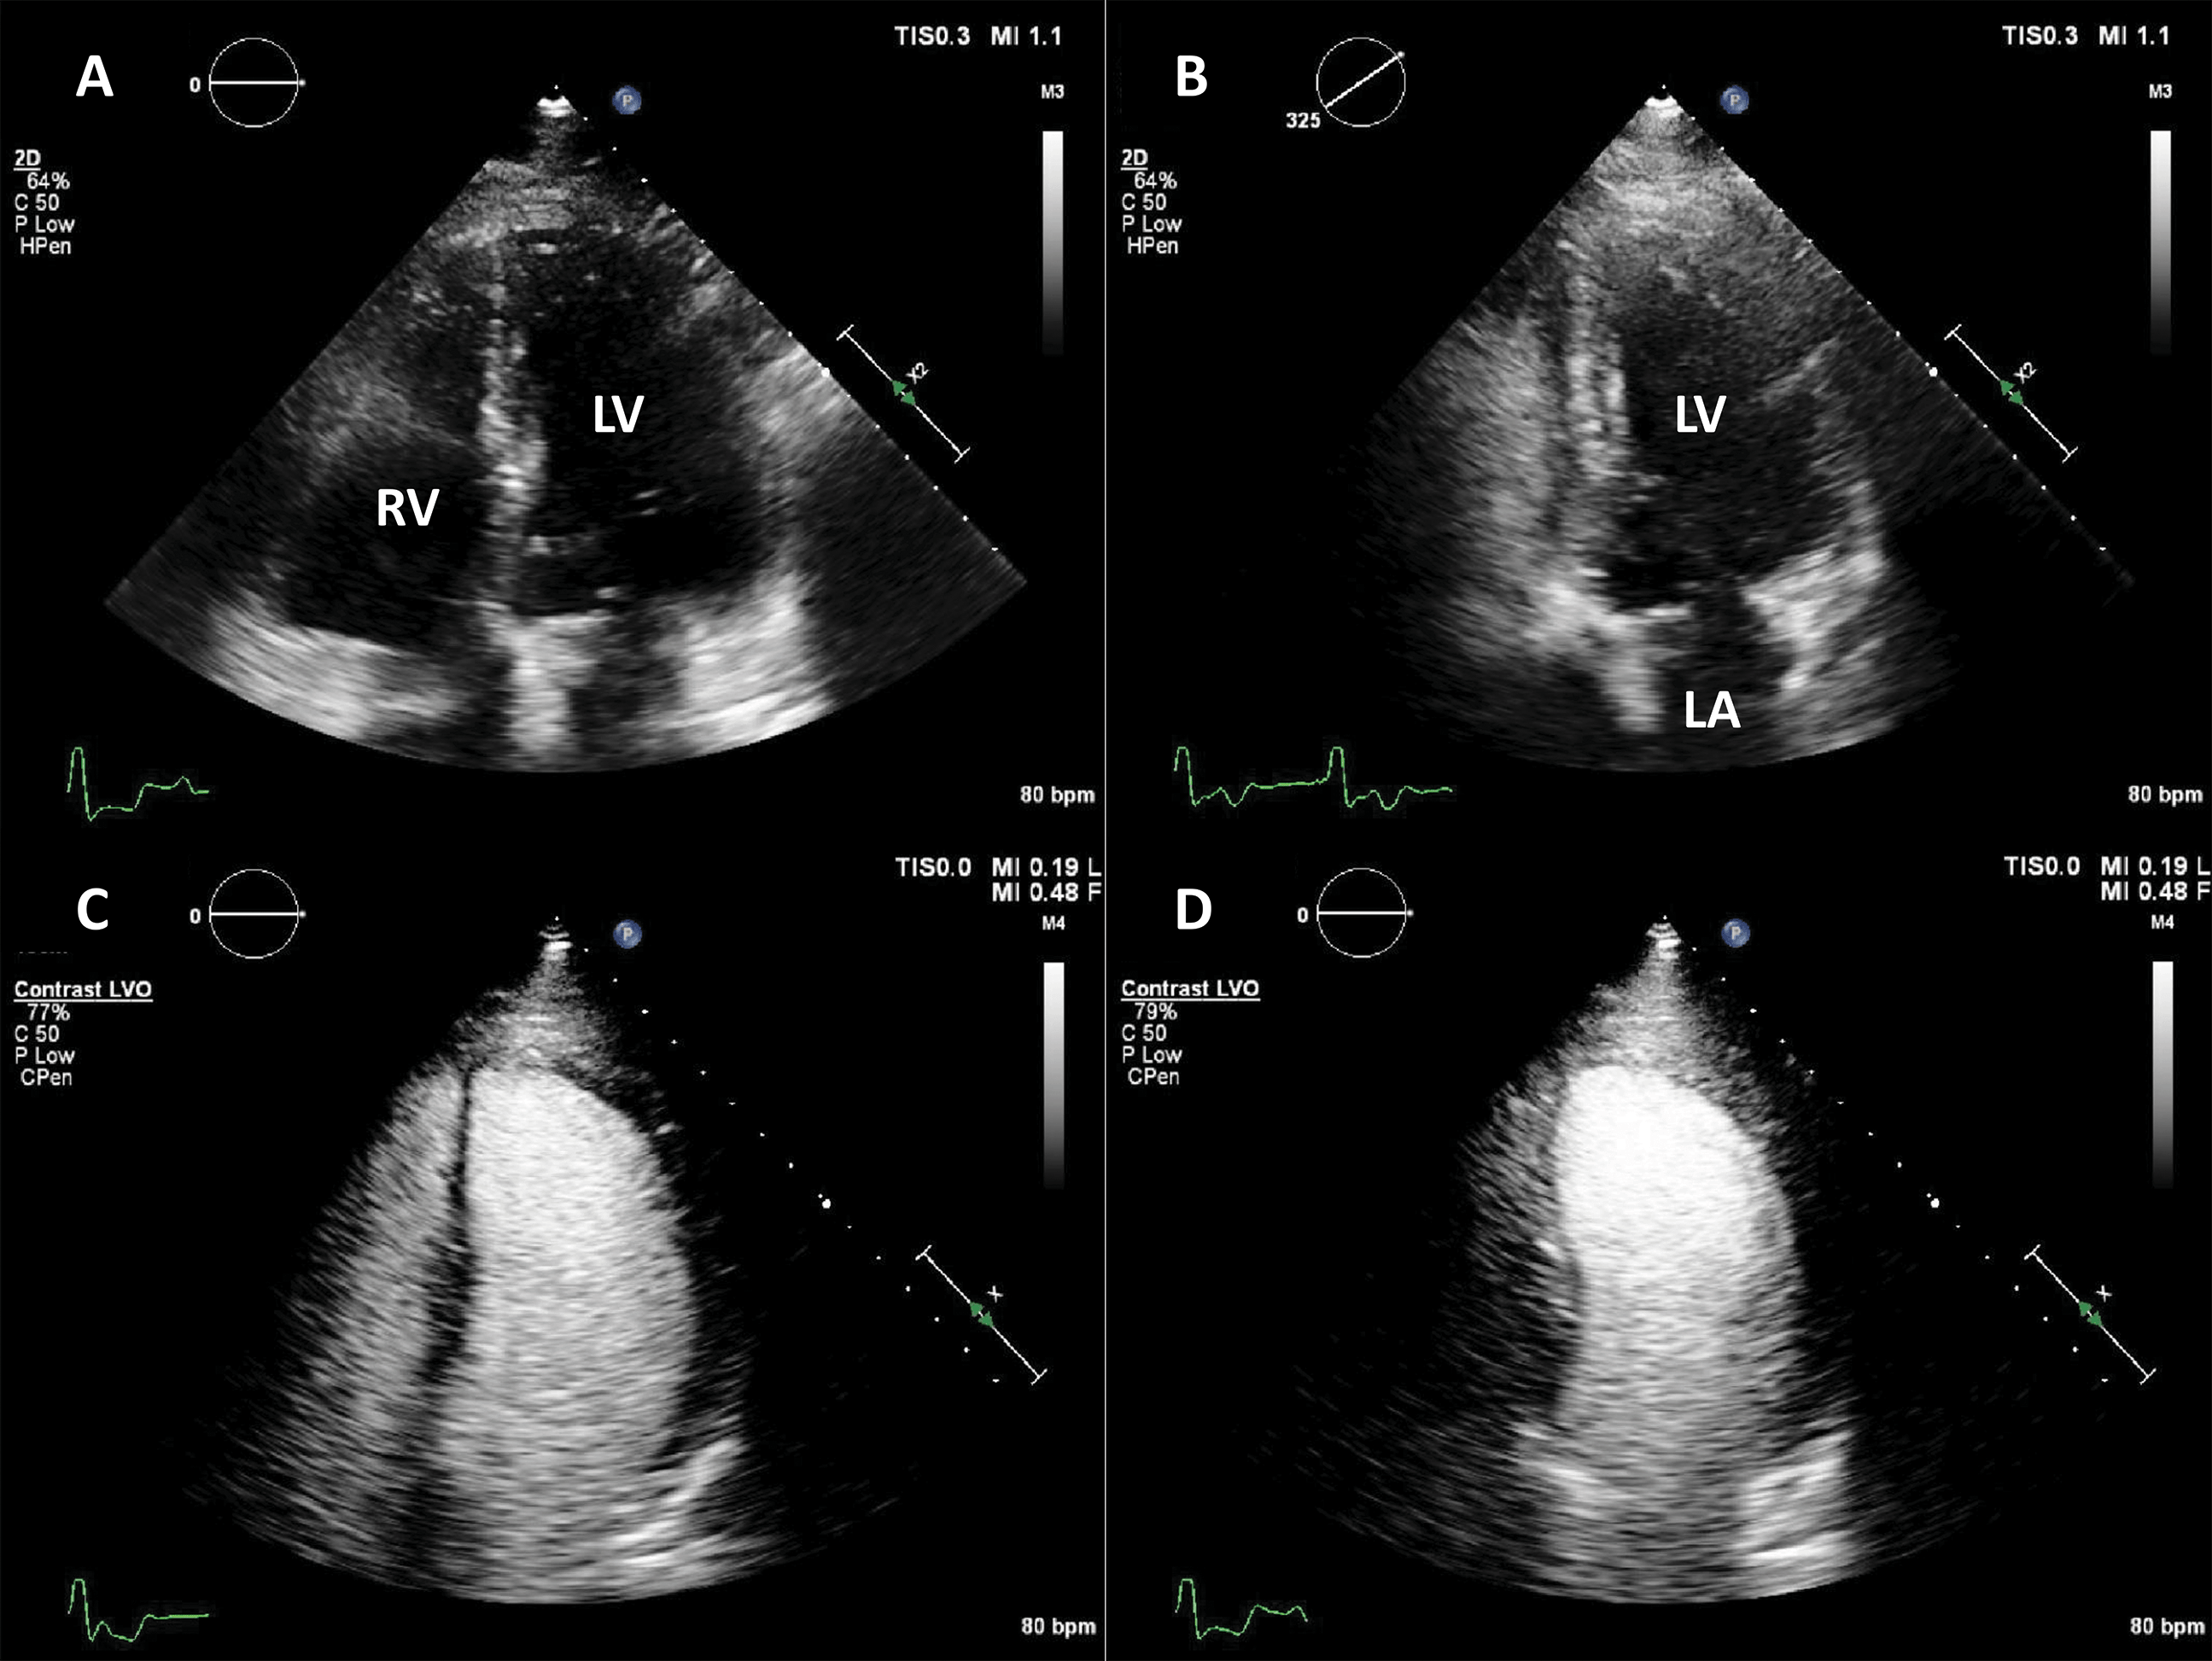

By using UEA, enhanced echocardiographic measurements of LV volumes and ejection fraction are very close to the reference cardiac magnetic resonance (CMR) values [11, 12], and significantly less variable as compared to unenhanced imaging, even if baseline images are of good quality [18]. This significant difference in quality, information and accuracy leads to a clinical impact on diagnosis and management [6, 19, 20]. Echocardiographic estimates of LV volume tend to be larger when using LVO, mainly because it aids the exclusion of trabeculae (Fig. 3), making the measurements closer to their CMR counterparts [13].

Fig. 3.Ejection fraction (EF) estimation. (A,B) Non-enhanced ultrasound images. The endocardium is not clearly visible in several segments (question marks), making the volumes difficult to assess. (C,D) Contrast-enhanced images. The endocardial border is clearly defined, allowing for a biplane volume estimation. Moreover, the LV end-diastolic volumes in contrast-enhanced images is notably larger than the one on the non-enhanced images, probably because of a combination of insufficient image quality on native images, and exclusion of trabeculae and papillary muscles on contrast images. Source: personal collection.